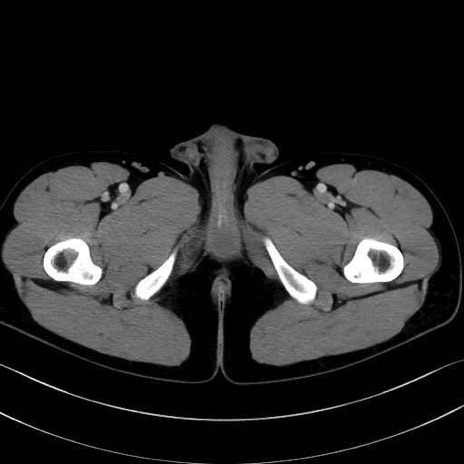

外閉鎖筋 (Obturator externus)

大腿方形筋 (Quadratus femoris)

5. 大腿前面(大腿四頭筋群・伸筋群)

縫工筋 (Sartorius)